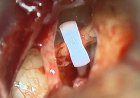

Insulinomas are rare and elusive pancreatic tumours that frequently evade routine...